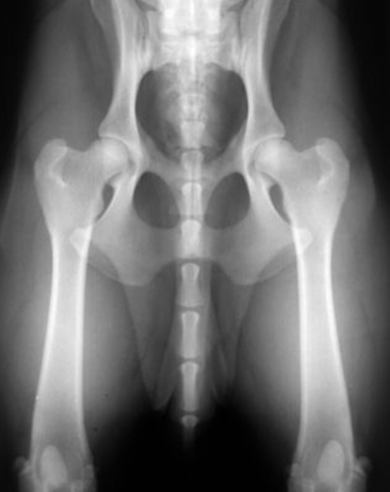

Koiran lonkat röntgenkuvassa

Pääkuva: Jukka Pätynen, oikealla oleva kuva on röntgenkuva koiran terveistä lonkista